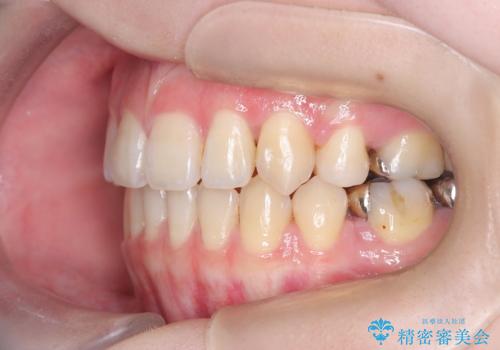

開咬や歯列のデコボコが改善され、見た目だけでなく咬み合わせの機能面も大きく向上し、大変ご満足いただけました。

また、治療期間も比較的短期間で終了することができました。